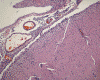

An autopsy limited to the brain was performed. The followings are representative photographs of the brain:

I. Semithin |